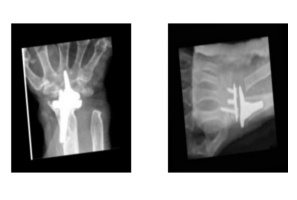

Worked as a Health data analyst and conducted through Exploratory data analysis on annotated clinical reports, create an intelligent data import module, optimizing SDoH dataset detection and ensuring seamless integration with a focus on simple systems for improved workflow.